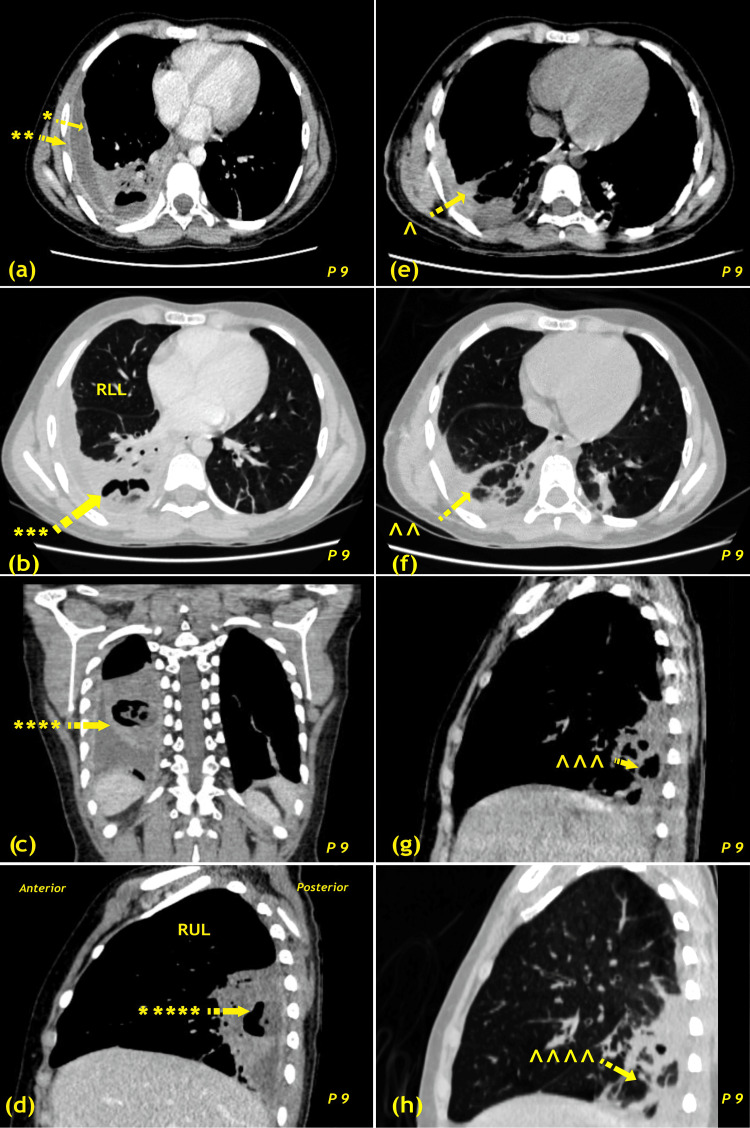

背景与目的胸膜脓肿是肺部感染的严重并发症,如果处理不当,发病率和死亡率都很高。虽然抗生素和引流在早期阶段是足够的,慢性脓胸往往需要手术干预。本研究评估了印度三级心脏中心早期开胸和去皮术治疗胸膜脓胸的结果。方法对2018 ~ 2024年9例早期开胸去皮患者进行回顾性观察研究。分析了人口统计学、影像学表现、病因、并发症、生存率和随访结果。采用Kaplan-Meier法评估生存率和无事件生存率。结果女性6例(66.7%),男性3例(33.3%)。4例患者行右侧去皮,4例左侧去皮,1例两侧去皮。6例(66.7%)有中度胸膜积液,3例(33.3%)有大量积液,9例(100%)胸膜增厚≥2 cm。病因包括非结核(TB; n = 7; 77.8%)和结核(n = 2; 22.2%)。术后出现并发症3例(33.3%),包括长时间漏气(n = 2)和创面浅表感染(n = 1)。1例(11.1%)患者死于院内肺炎、急性呼吸窘迫综合征和感染性休克。Kaplan-Meier估计30天生存率为88.9%,12个月时保持稳定。12个月无事件生存率为66.7%。中位住院时间为12天(范围8-21天)。在3 - 12个月的随访中,所有幸存者均表现出令人满意的肺再扩张,无复发。结论早期开胸去皮术是治疗晚期胸膜脓肿安全有效的方法,具有良好的生存和功能预后。尽管微创手术取得了进展,但对于某些患者,特别是结核病流行地区的患者,开胸手术仍然是必不可少的。

Background and aim Pleural empyema remains a serious complication of pulmonary infections, with high morbidity and mortality if not managed effectively. While antibiotics and drainage are sufficient in the early stages, chronic empyema often requires surgical intervention. This study evaluates the outcomes of early thoracotomy and decortication for pleural empyema at a tertiary cardiac center in India. Methods A retrospective observational study was conducted on nine patients who underwent early thoracotomy and decortication between 2018 and 2024. Demographics, radiological findings, etiology, complications, survival, and follow-up outcomes were analyzed. Survival and event-free survival were assessed using the Kaplan-Meier method. Results Six patients were female (66.7%), and three were male (33.3%). Four patients underwent right-sided, four left-sided, and one bilateral decortication. Six patients (66.7%) had moderate pleural fluid, three (33.3%) had large fluid collections, and all nine (100%) had pleural thickening ≥2 cm. Etiologies included non-tuberculosis (TB; n = 7; 77.8%) and TB (n = 2; 22.2%). Postoperative complications occurred in three patients (33.3%), including prolonged air leak (n = 2) and superficial wound infection (n = 1). One patient (11.1%) died from nosocomial pneumonia, acute respiratory distress syndrome, and septic shock. Kaplan-Meier estimated survival probability was 88.9% at 30 days and remained stable at 12 months. Event-free survival at 12 months was 66.7%. The median hospital stay was 12 days (range, 8-21). All survivors demonstrated satisfactory lung re-expansion with no recurrence during three to 12 months of follow-up. Conclusions Early thoracotomy and decortication is a safe and effective treatment for advanced-stage pleural empyema, yielding favorable survival and functional outcomes. Despite advances in minimally invasive surgery, thoracotomy remains indispensable for selected patients, particularly in TB-endemic regions.